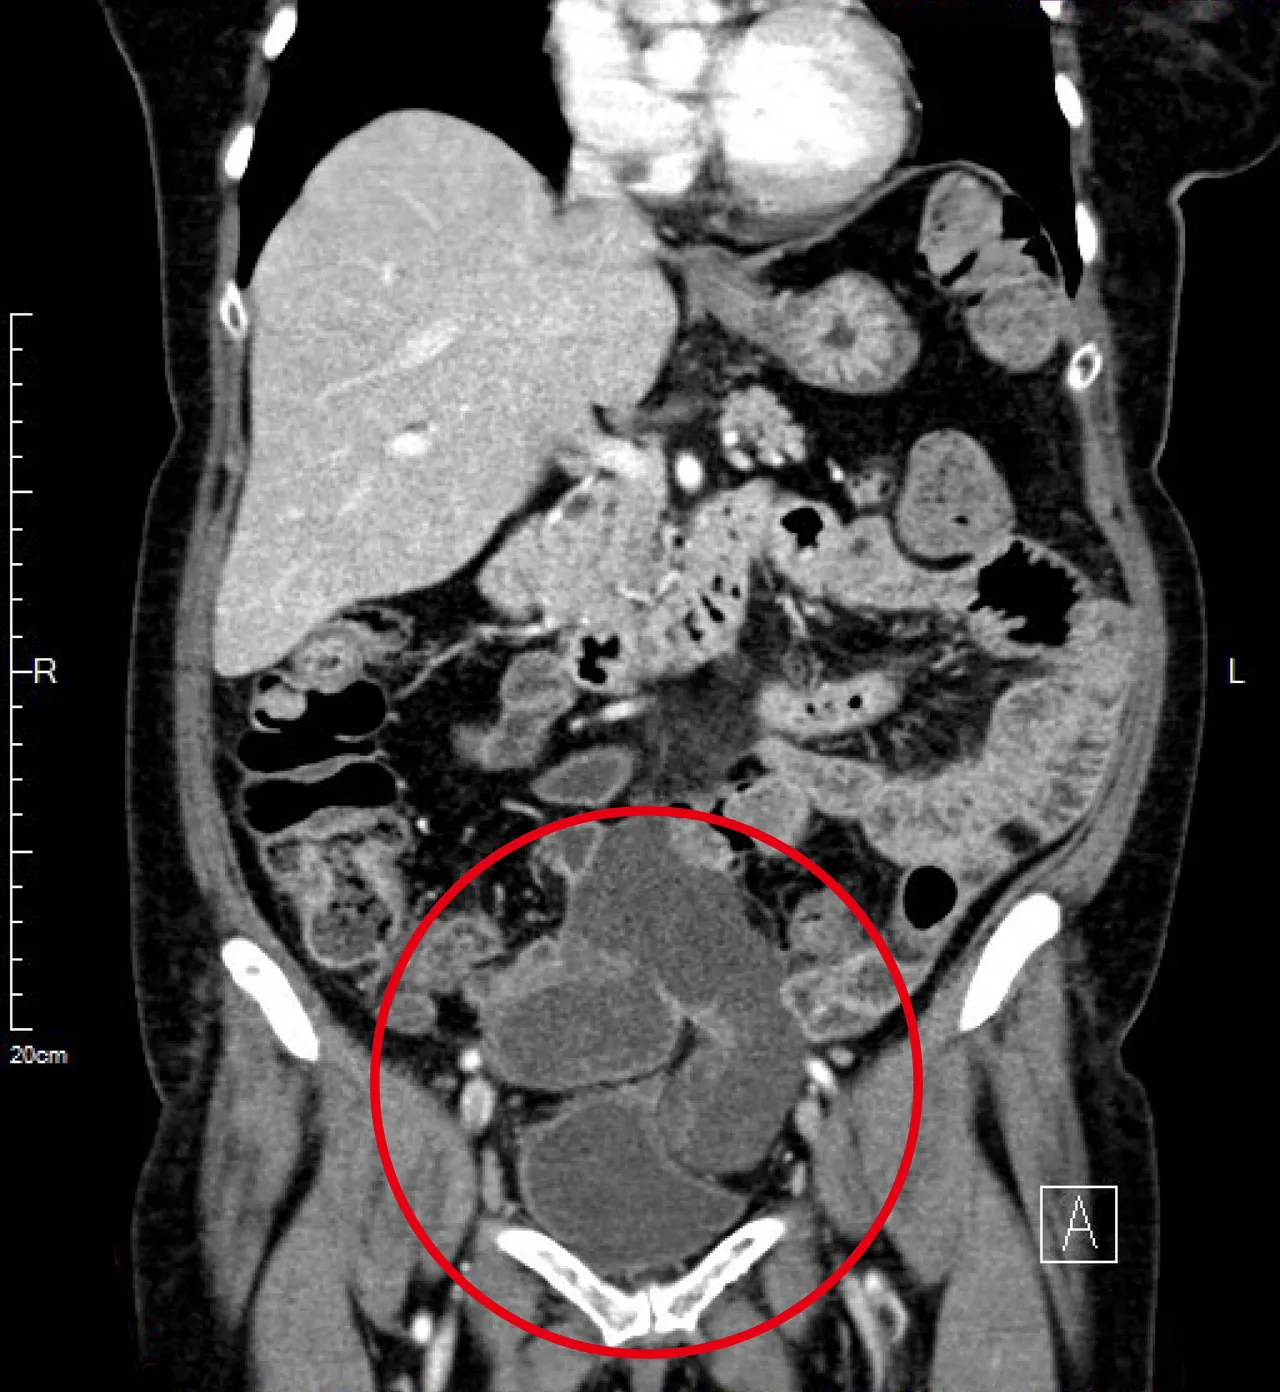

露米因腹痛在帛琉被診斷出結腸癌,2022年4月經馬偕醫院國際醫療中心安排轉診來台治療,進一步檢查發現是大腸直腸癌合併卵巢與腹膜轉移。大腸直腸外科與腹膜癌治療團隊主治醫師陳建勳表示,大腸直腸癌合併腹膜轉移發生比例雖然不高,治療上卻較為複雜。

馬偕為露米安排的「腹腔腫瘤減積配合溫熱化學治療」計畫中,手術由陳建勳、婦產部主治醫師陳禎瑞、一般外科主治醫師何恭誠三位合作,同時進行次全大腸切除、子宮與卵巢切除、腹膜切除、大網膜切除手術等,腹腔內手術完成後,緊接著執行90分鐘的腹腔內高溫治療(腹腔溫熱灌注化療,HIPEC),總計手術時間10小時。